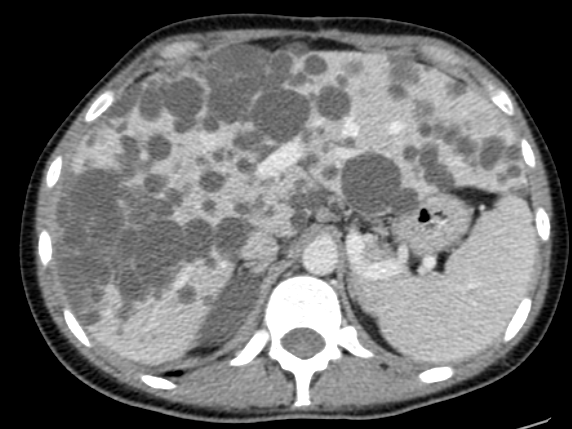

Enfermedad poliquística

La presencia de quistes hepáticos múltiples puede ser un indicador de la enfermedad poliquística del adulto, la cual tiene un carácter autosómico dominante en su patrón hereditario. Esta condición puede manifestarse con la formación de quistes no solo en el hígado sino también en los riñones, siendo conocida como poliquistosis renal cuando ambas están presentes.

La enfermedad poliquística hepática en adultos suele transcurrir de manera asintomática, aunque algunos pacientes pueden experimentar síntomas como un dolor sordo en el hipocondrio derecho, sensación de plenitud, percepción de una masa abdominal y aumento del perímetro abdominal.

Con el transcurso del tiempo y el aumento en el número y tamaño de los quistes, estos pueden volverse palpables durante la exploración física. En estudios de imagen como la ecografía, los quistes hepáticos aparecen como estructuras llenas de líquido, sin ecos internos, a menos que ocurra sangrado o infección.

En la ecografía, una herramienta diagnóstica habitual para quistes hepáticos, se observan varios quistes llenos de líquido, sin ecos internos, a menos que se presenten complicaciones como sangrado o infección.